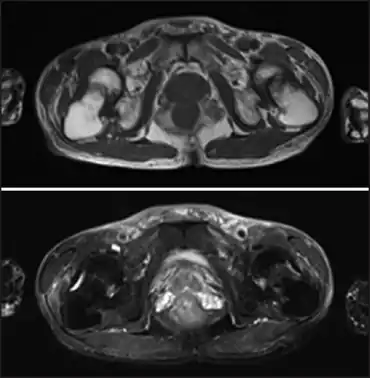

| Fanconi syndrome due to adefovir-image demonstrates low-intensity femoral neck fractures and high-intensity bone edema in both femoral necks | |